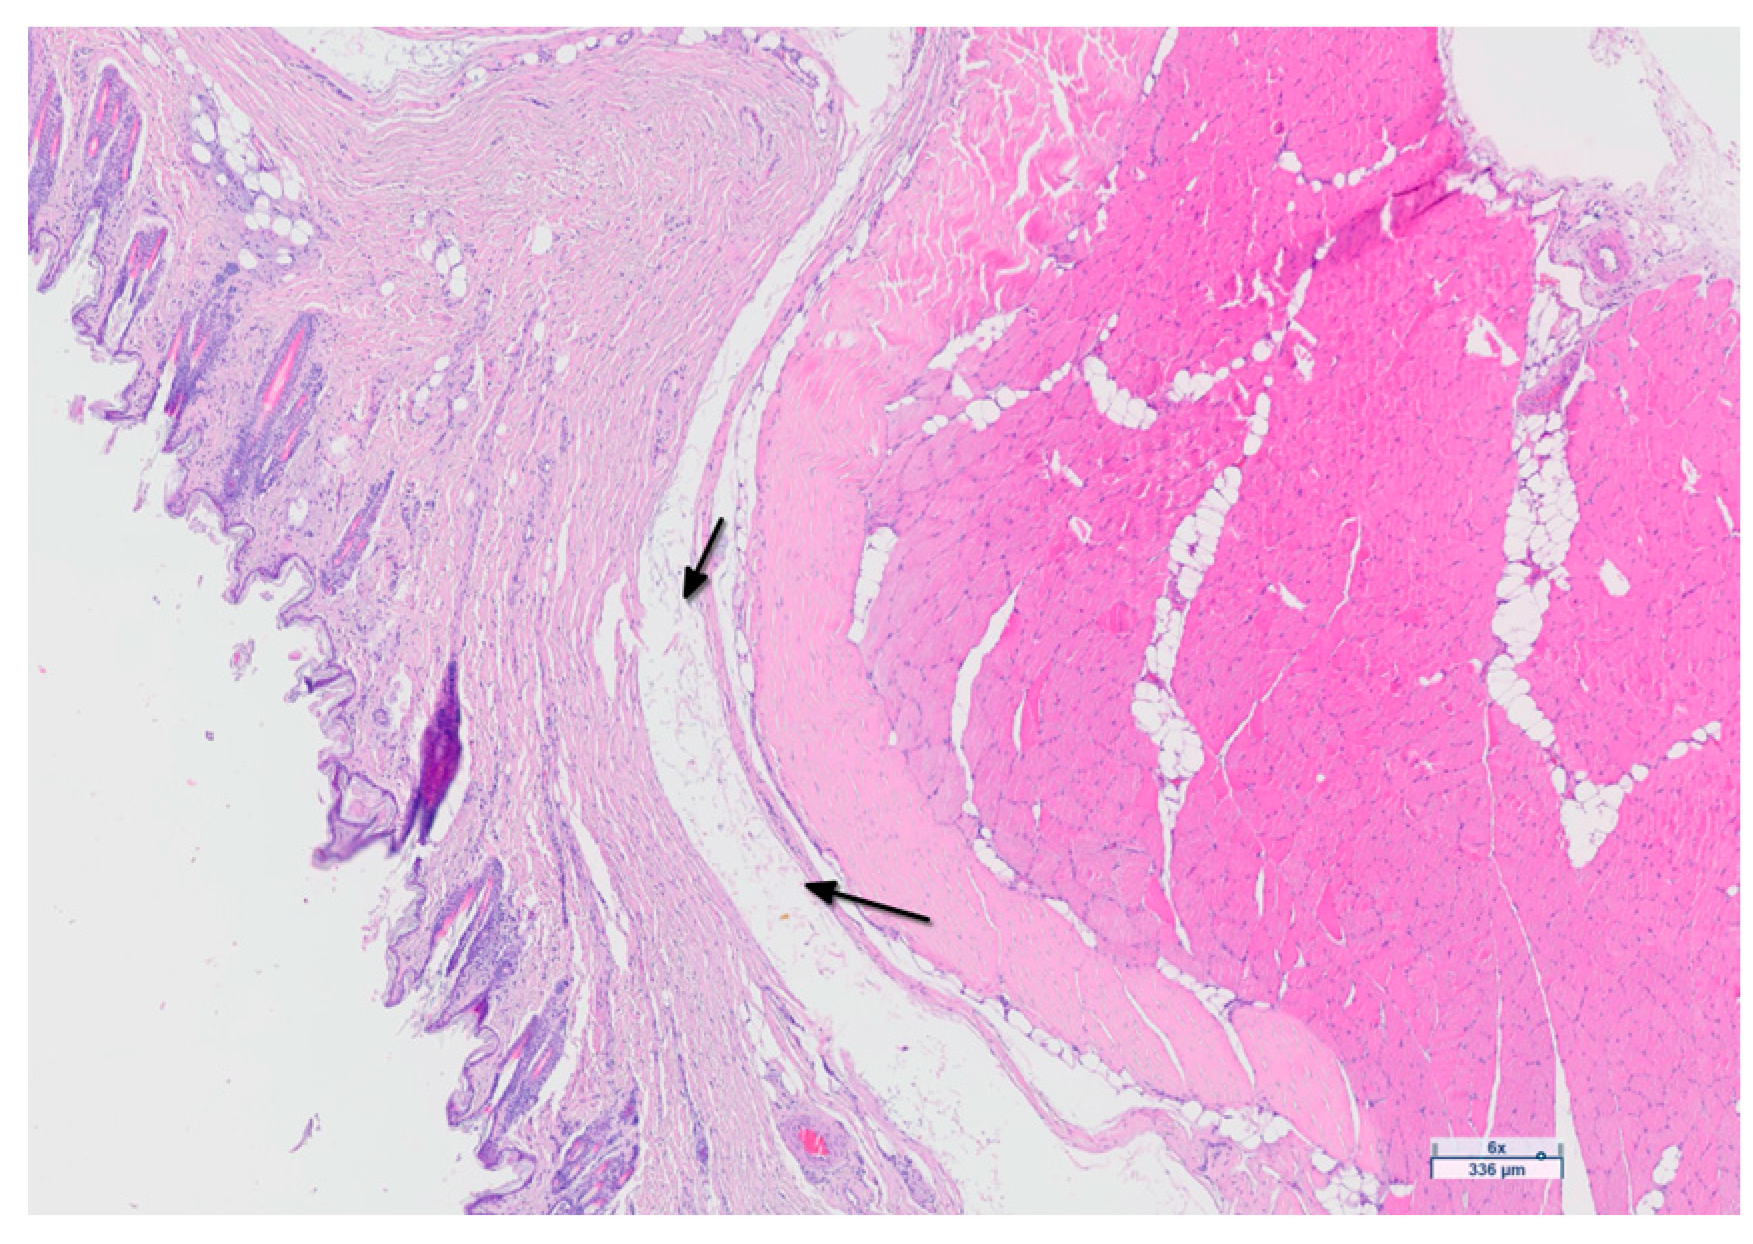

3.5. Histological Analysis